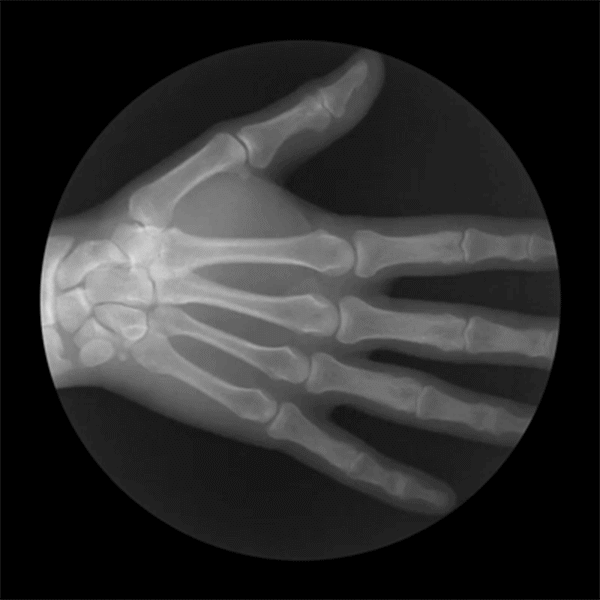

手的骨骼結(jié)構(gòu),手由緊密排列的8塊腕骨、5塊長(zhǎng)形的掌骨和14塊指骨構(gòu)成,整只手共有27塊骨骼、16個(gè)關(guān)節(jié)。

手部結(jié)構(gòu)包括腕、掌、指三部分。腕部連接手與前臂。腕部骨骼與手的其他骨骼連在一起,筑成一塊體積,腕和手一起活動(dòng)。前臂的背面、腕、掌、指呈“降階式”。要注意腕部在運(yùn)動(dòng)中的形狀變化,手腕在造型中很重要但是常常被忽略掉,了解手的相互的關(guān)聯(lián)才是畫好手的基礎(chǔ)。

正面,手掌占整個(gè)手部長(zhǎng)度的3/5,成正方形:四指占2/5,且每根手指中的三段指骨比例都是相等的:拇指居手掌的中段和食指第一節(jié)的中段部位,且兩段指骨比例相等。

背面,手掌與四指的比例是相等的,四指中每根手指的第一節(jié)的比例與第二,三節(jié)的比例總和是相等的,第二節(jié)與第三節(jié)也是相等的:拇指比例位置基本不變。